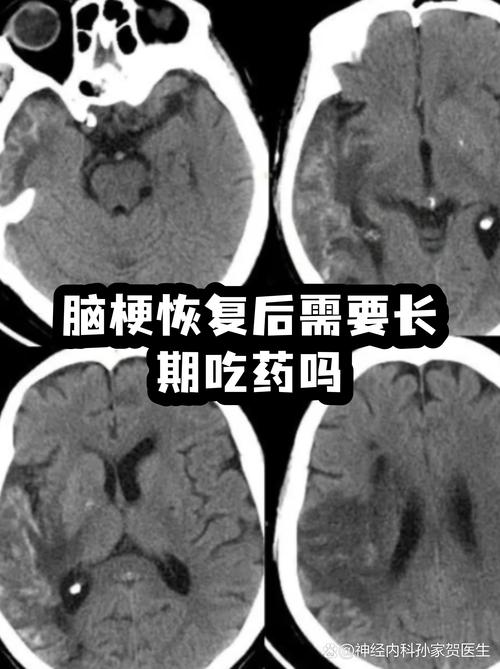

这是一个非常重要且常见的问题,答案是:绝大多数情况下,即使脑梗“好了”,也需要长期、甚至终身服药。

(图片来源网络,侵删)

下面我将为您详细解释为什么,以及具体需要服用哪些药物,希望能帮助您和您的家人更好地理解和应对。